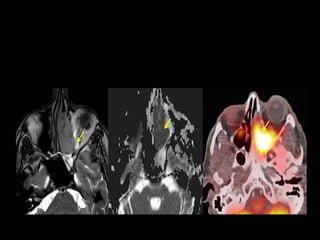

MRI: Heterogeneous, intermediate to high signal on T2W, flow voids +

• Axial section, T1-weighted magnetic resonance image shows a large, well-defined

mass (arrow) in the region of the pterygo-maxillary fissure and sphenopalatine

foramen on the right side with a heterogenous intensity.